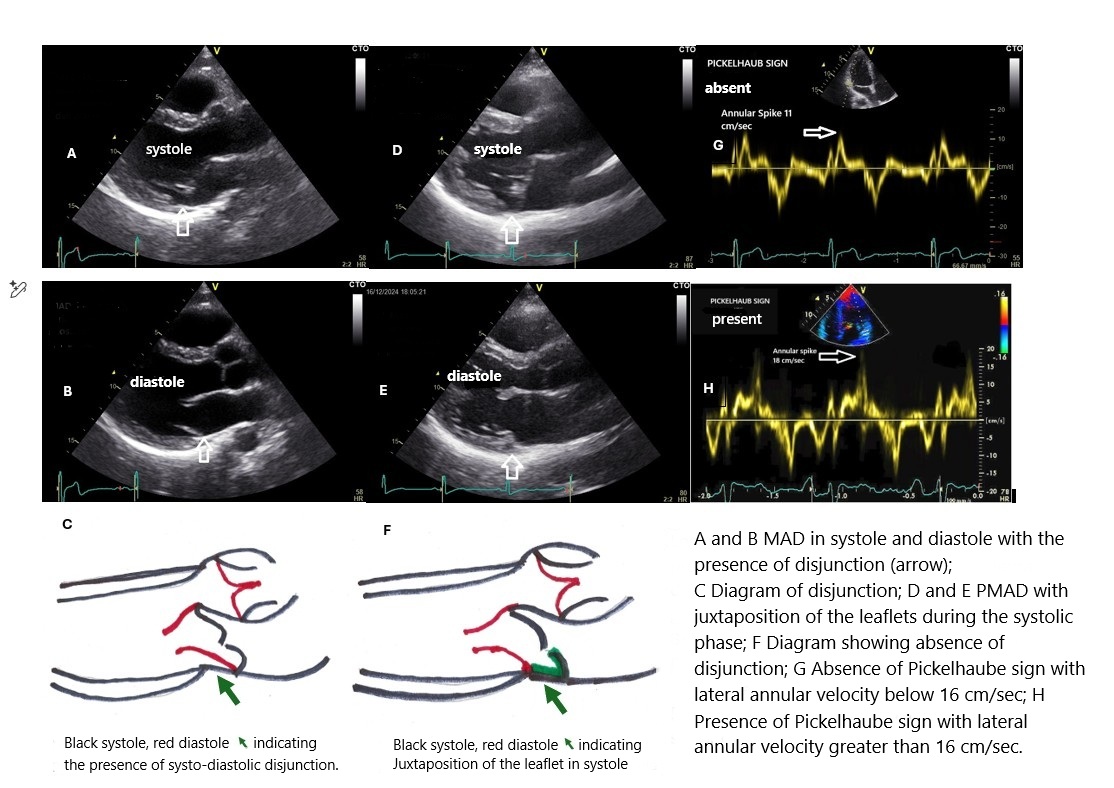

Aim of the study : To evaluate arrhythmic risk in a group of young athletes with Mitral Valve Prolapse (MVP) by analyzing the correlation between arrhythmic events and specific echocardiographic markers, particularly Mitral Annular Disjunction (MAD), pseudo Mitral Annular Disjunction (PMAD), and the Pickelhaube sign (PS). Methods : Eleven athletes aged 15 to 28 years (6 males, 5 females) with a diagnosis of MVP were studied. All subjects underwent echocardiography (Echo), ECG Holter monitoring, and exercise testing. The echocardiogram specifically assessed: MAD, defined as an abnormal systolic–diastolic separation between the mitral annulus and the left ventricular myocardium, typically located in the posterior wall; PMAD, showing separation limited to the systolic phase, and therefore appearing due to the juxtaposition of the posterior leaflet to the atrial wall, whereas MAD results from an actual atrial insertion of the annulus; PS, a systolic peak velocity >16 cm/s on Tissue Doppler Imaging (TDI) at the lateral mitral annulus; Speckle tracking (ST) with assessment of Post-Systolic Shortening (PSS), defined as systolic shortening occurring after aortic valve closure. Arrhythmic burden was evaluated through ECG Holter monitoring and exercise testing. Results : The PS was observed in 4 athletes: 2 with PMAD, 1 with MAD, and 1 with isolated MVP. Athletes positive for PS showed a higher incidence of arrhythmic events compared to those without PS. Although MAD and PMAD were associated with abnormal mechanical patterns of the mitral annulus, the PS emerged as the marker most strongly correlated with arrhythmic burden. Moreover, athletes with PS showed PSS localized in the infero-posterolateral segments. Discussion : The observed correlation between arrhythmic burden and PS may be attributed to PSS. It is known that PSS is a marker strongly associated with adverse clinical events, as widely documented in ischemic heart disease. This parallel suggests that PSS may be one of the mechanisms through which PS contributes to increased arrhythmic vulnerability in subjects with MVP. Conclusions : In our cohort of young athletes with MVP, the presence of the Pickelhaube sign represents the main echocardiographic indicator associated with an increased arrhythmic risk. Including its assessment in the screening protocol for athletes with MVP may improve risk stratification and guide clinical follow-up.